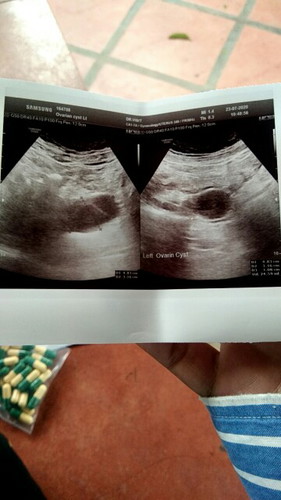

รบกวนขอสอบถามแม่ๆหน่อยค่ะพอดีเรามีบุตรยากปล่อยมาแล้ว6ปีแล้วตั้งครรภ์ปี2563ได้4เดือนแล้วก็ได้แท้งไป(เนื่องจากหมอให้ความเห็นว่าหัวใจเด็กหยุดเต้นและเกี่ยวกับโครโมโซนอะไรนี่ละค่ะและได้ทำการขูดมดลูกไปและให้พักก่อน1ปีค่อยตั้งครรภ์ใหม่แต่พอครบปีเราได้ไปตรวจอัลตร้าซาด์มดลูกและรังไข่และพบว่าเป็นชีสในรังไข่ด้านซ้าย4.7เซนหมอบอกว่าไม่อันตรายจะให้ยาคุมกินแต่เราต้องการมีบุตรหมอเลยไม่ได้จ่ายยาให้และพยาบาลบอกว่าถ้าตั้งครรถ์ก็ไม่อันตราย#เราเลยไม่แน่ใจว่าเราตั้งครรภ์ได้ไหมและถ้ามีอีกจะแท้งเหมือนเดิมหรือเปล่าเราครวรักษาชีสให้หายก่อนไหมหรือตั้งครรภ์ได้เลยขอคำปรึกษาหน่อยค่ะไม่มีประสบกานมาก่อน(ป.ลอยากมีบุตรมากอายุ34แล้วค่ะ